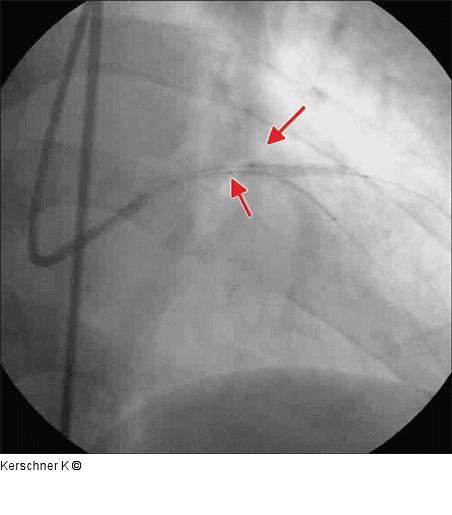

Abbildung 6: Stentimplantation - LAD Stentimplantation LAD / R. diagonalis in Crush-Technik. R. diagonalis Taxus Express 2 (Boston Scientific) 2,75 / 24 mm, 14 atm. |

Stentimplantation LAD / R. diagonalis in Crush-Technik. R. diagonalis Taxus Express 2 (Boston Scientific) 2,75 / 24 mm, 14 atm. |